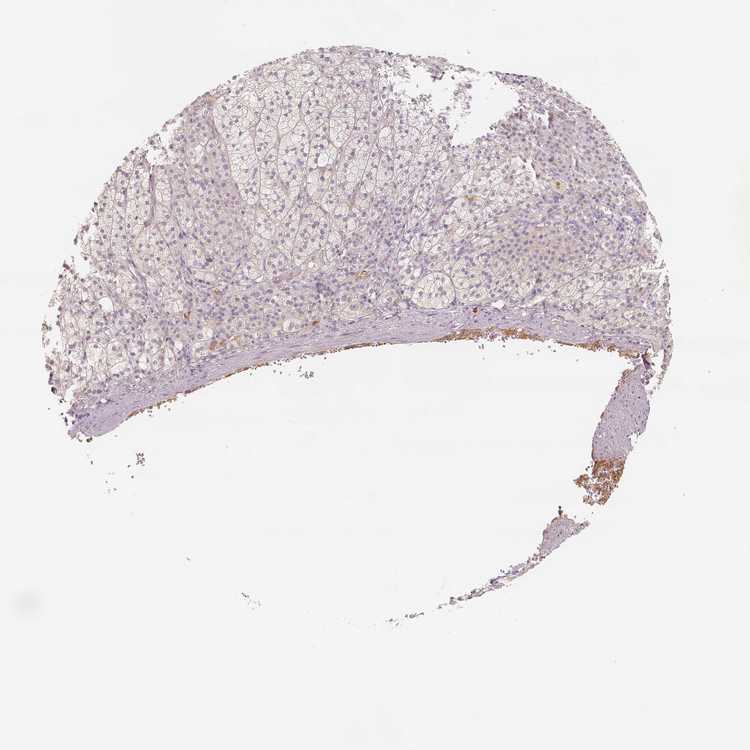

ADRENAL GLAND - Antibody stainingi

Antibody staining in the annotated cell types in the current human tissue is reported as not detected, low, medium, or high, based on conventional immunohistochemistry profiling in selected tissues. This score is based on the combination of the staining intensity and fraction of stained cells.

Each image is clickable and will lead to virtual microscopy that enables deeper exploration of all samples and also displays staining intensity scores, fraction scores and subcellular localization as well as patient and tissue information for each sample.

Antibody HPA006026

Glandular cells Low